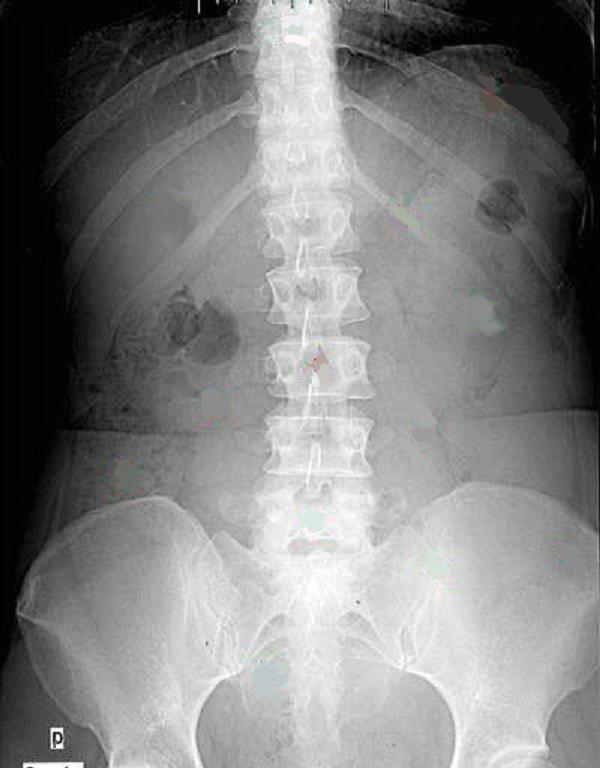

Le cliche de ASP

Sur les films d’ASP, la rate, de densité

hydrique, est surtout visible au niveau de

son bord interne en raison des superpositions colique et la

poche d' air gastrique.

Lorsqu’elle augmente de volume ,

elle se presente comme une densité arrondie de l’hypocondre

gauche vers le flanc gauche, améliorant

la vision du rein gauche , le côlon et l’estomac

apparaissent refoulés en bas et en dedans. On peut en

possible d’apprécier le grand axe de la rate sur l’ASP par

mesure la distance entre la coupole diaphragmatique gauche

et le point du pole inferieure de la rate . Ce chiffre est

diminué de 2cm correspondance au grand axe réel de la rate .

Normalemenmt 14cm -2cm = 12cm et on peut en surgerer une

splenomegalie par la mesure globale 16cm -2cm = 14cm . En

dehord dẻ La cliche1 de face ASP peut utilisé

identifier une ou plusieurs calcifications spléniques.

Image

radiologique schematisé normale du cliché de face

de l'abdomen ( ASP ). . La rate est situé a gauche dans

la loge sous diaphragmatique gauche (2) |

Le cliche de face seul peut

etre declenche l'ombre de la rate situé a gauche ,

sous diaphragmatique et occupant la loge sous

phrenique gauche . On peut declenche1 encore des calcification

de la rate dans quelque lesions

inflamatoire ou tumorales de la rate |